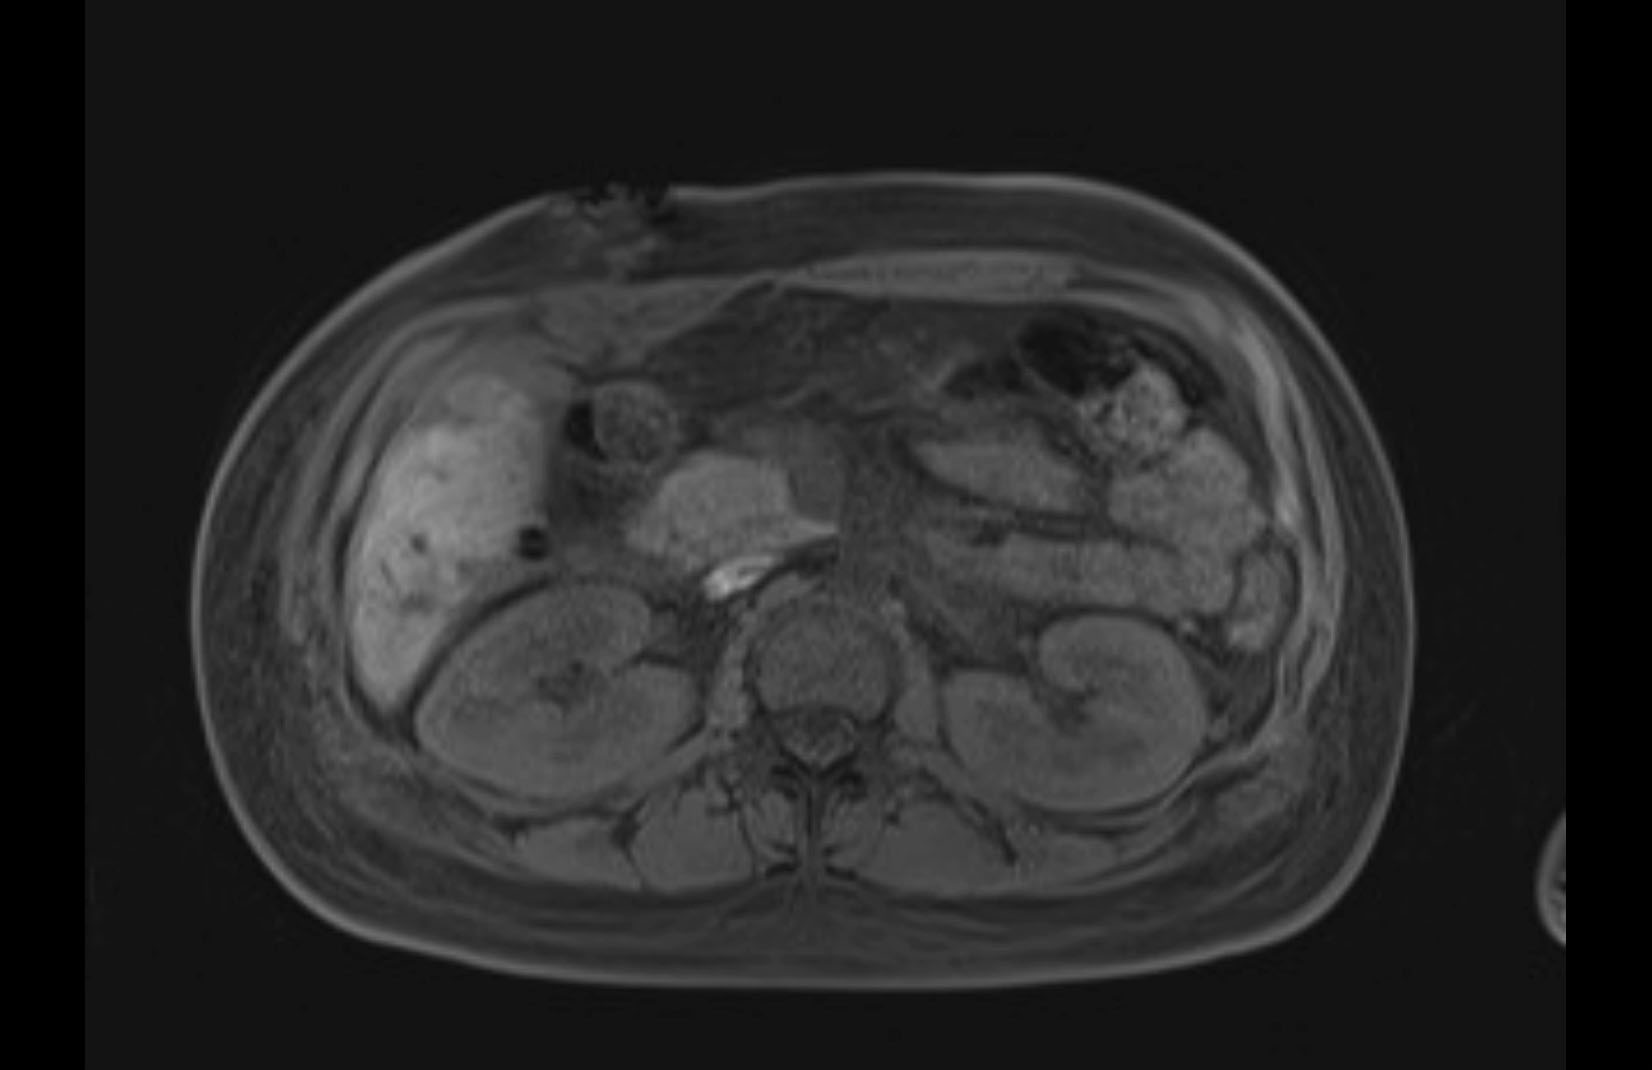

MRI T1